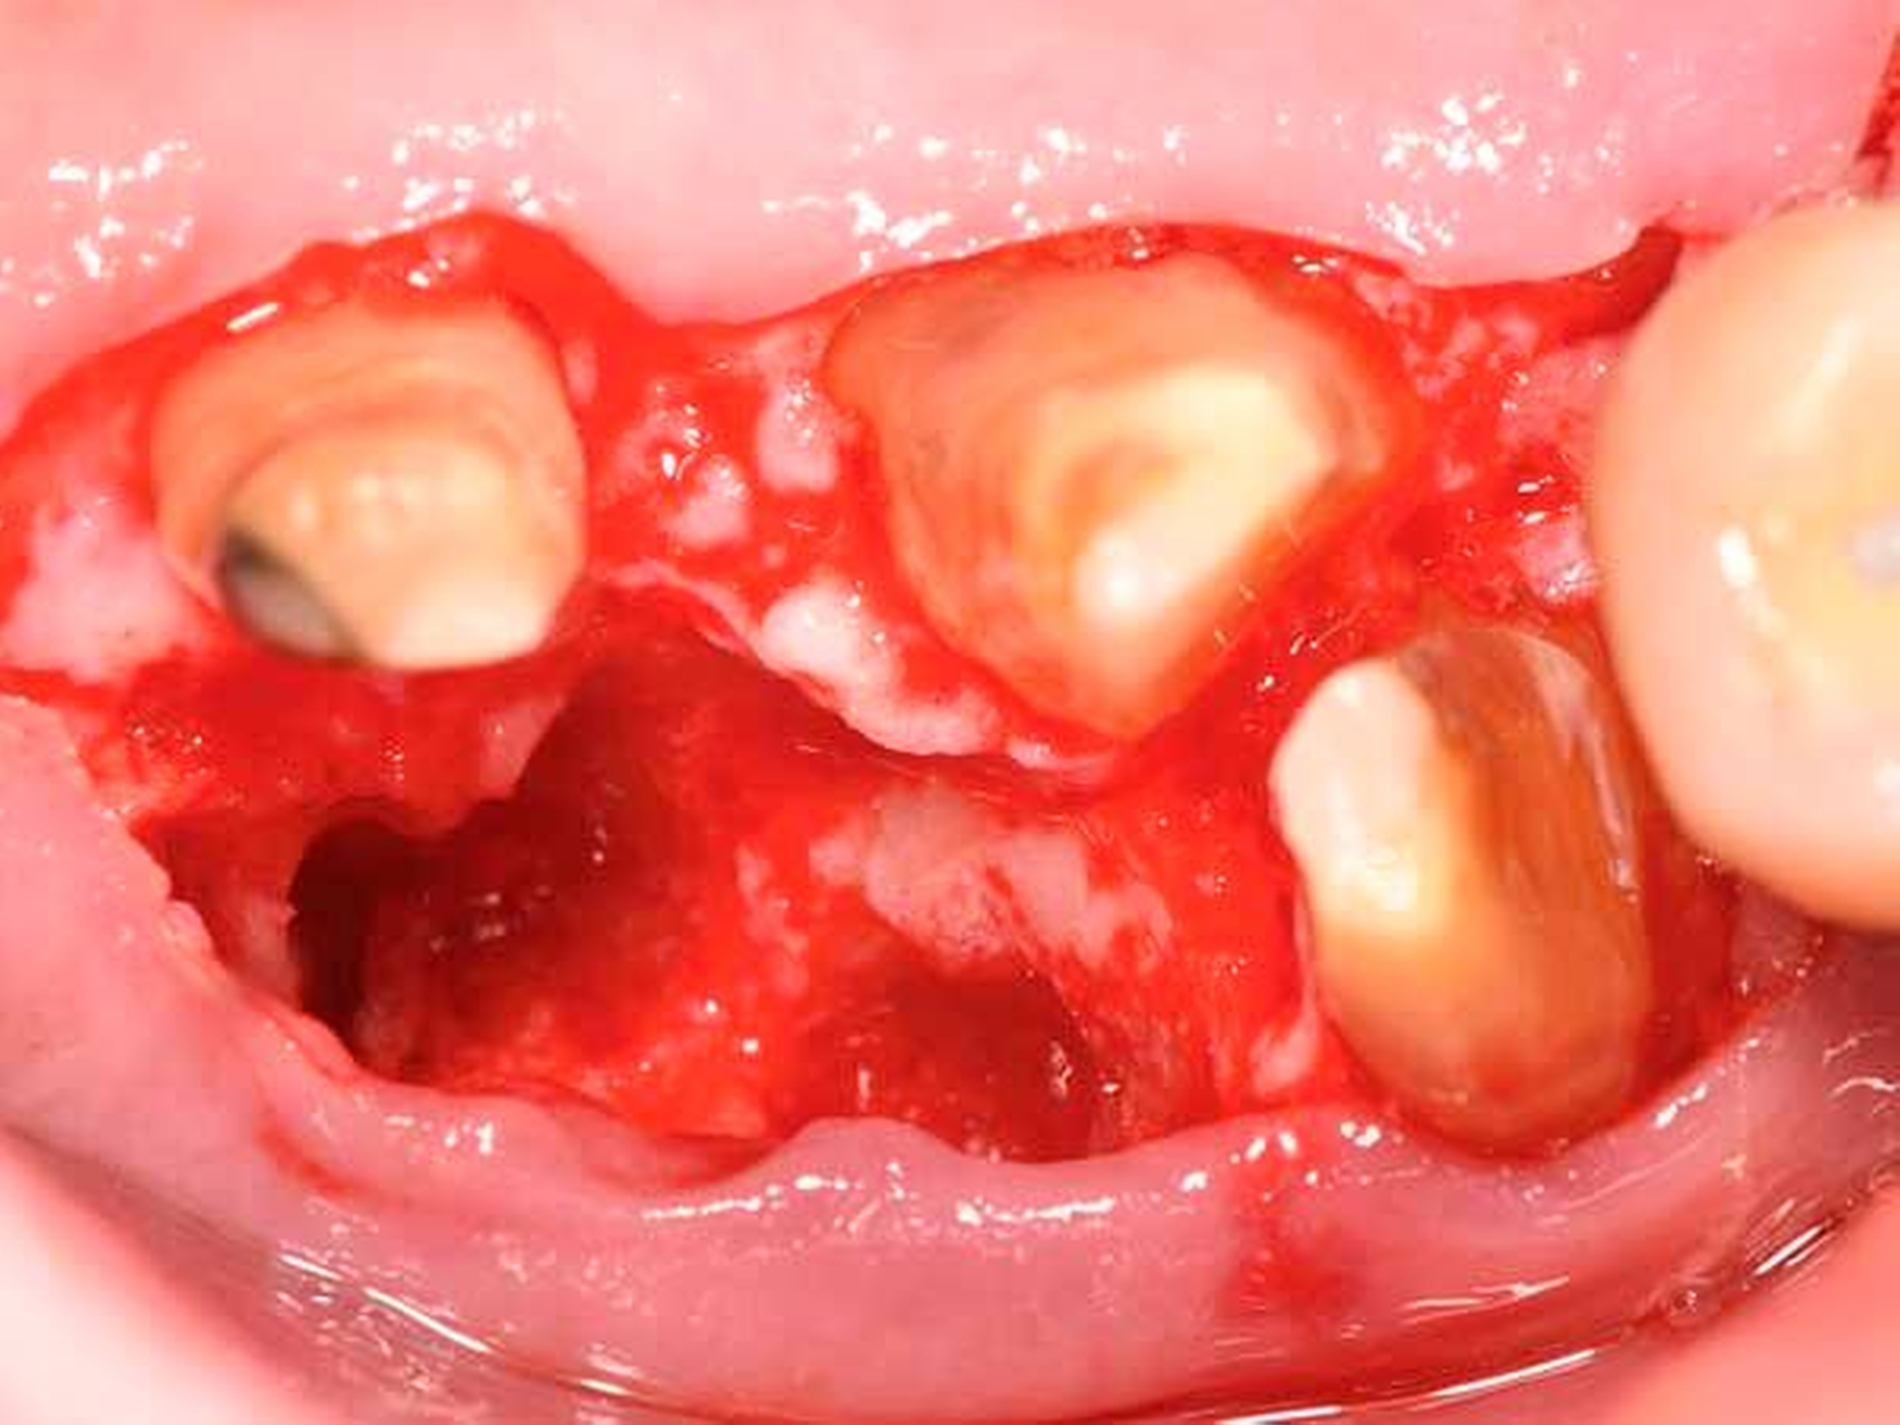

Daher gewinnen gerade im posterioren Oberkiefer oder bei Vorliegen einer durchgängigen Furkation resektive Maßnahmen wie die Amputation einer oder mehrerer Wurzeln (Abbildung 8b bis 8d), die Prämolarisierung sowie die Tunnelierung wieder an Bedeutung. Diese Maßnahmen sind klinisch herausfordernd, da neben einer hochwertigen parodontologischen Versorgung eine adäquate endodontologische Therapie und eine sinnvolle restaurative Versorgung für den Langzeiterfolg notwendig sind. Nachdem Autoren aus Italien [Carnevale et al., 1998] und den USA [Fugazzotto, 2001] schon länger von hervorragenden Überlebensraten wurzelamputierter Molaren berichtet haben, liegen nun auch aus Deutschland retrospektive Daten über bis zu 30 Jahre vor, nach denen ein Wurzel-amputierter Molar eine mediane Überlebenszeit von etwa 20 Jahren aufweist [Derks et al., 2017].